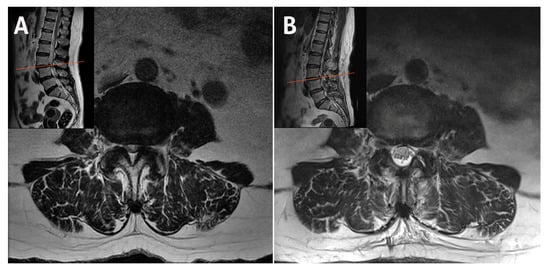

2.1. Case 1: Bilateral–Contralateral Decompression in Upper Lumbar Stenosis

| 1 | 67 | M | Upper Lumbar Stenosis | L3–L4 | 55 | 6 | 2 | 7 | 1 | 48 | 16 | None | 6 |